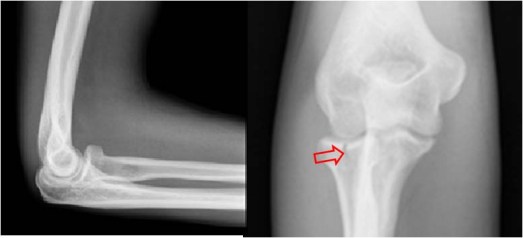

SIGNO DEL SUPINADOR CORTO

Signo de fractura de la porción proximal del radio, especialmente del cuello, que consiste en el ensanchamiento, borramiento o desplazamiento de la línea grasa que cubre al músculo supinador corto.

En la imagen el plano graso está borrado (compara con la imagen normal, abajo). La flecha señala la fractura de la cabeza radial. En ocasiones está presente el signo y no es visible la fractura en las proyecciones convencionales, lo que nos obligará a realizar proyecciones adicionales o TC buscando una fractura oculta.

Radiografía lateral de codo normal que permite ver el plano graso que limita al músculo supinador corto (flechas).